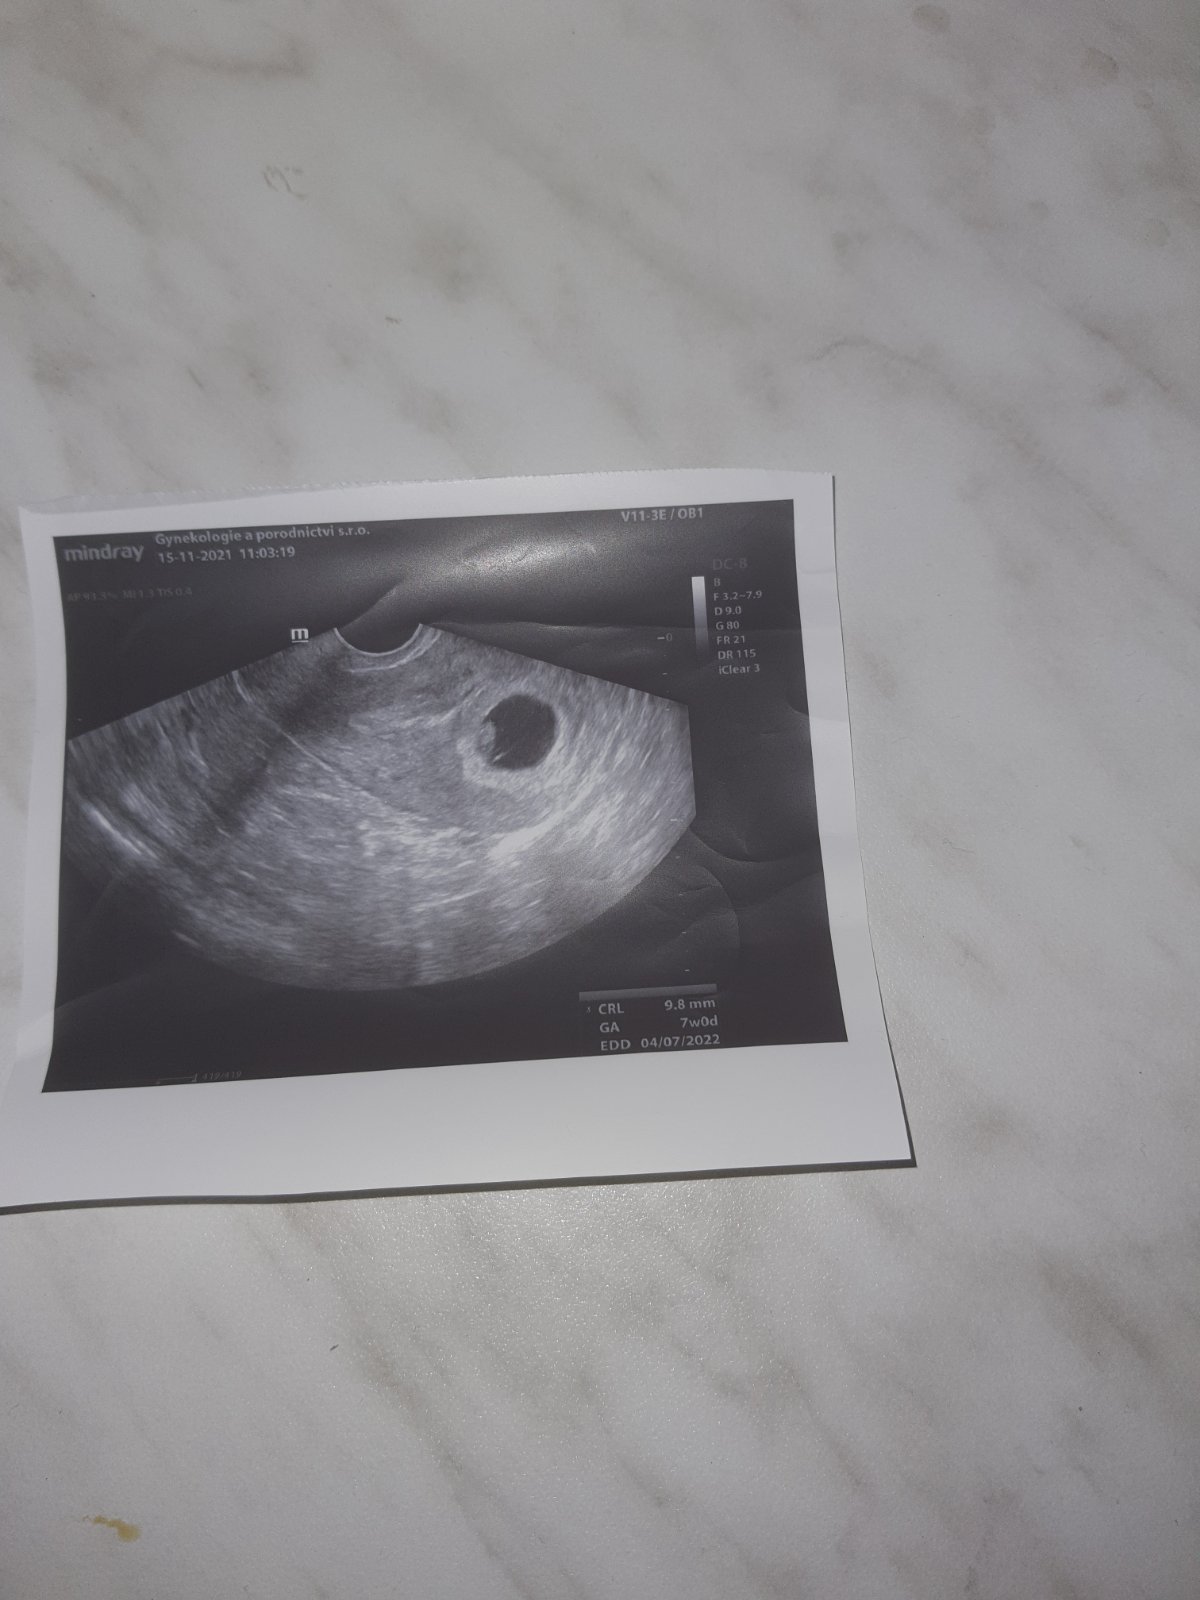

Dnes 8+0 dle posledního ultrazvuku...

@misaa56 Dobré ranko, tak dnes takto🥰